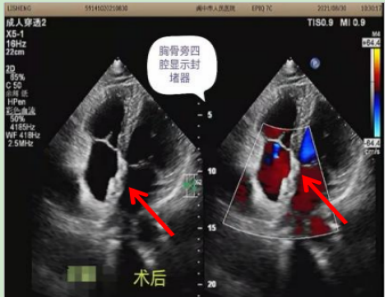

术后超声心动图